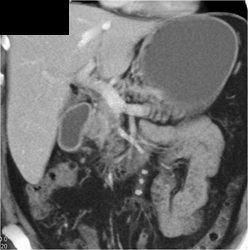

Linitis Plastica